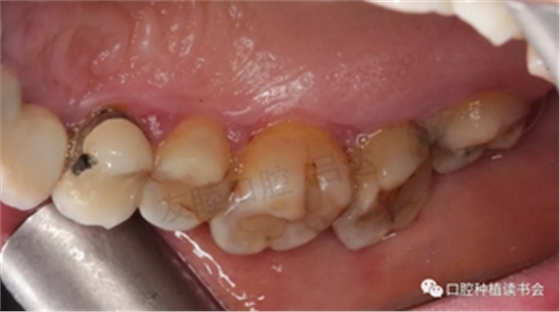

檢查視角轉(zhuǎn)向整個(gè)口腔,發(fā)現(xiàn)有廣泛牙周感染。齦乳頭處可探及齦下牙石,探診深度PD:4-6mm,出血指數(shù)BI:3-4。(圖5-圖10)

圖10 46種植體頰側(cè)中央粘膜邊緣膿腫,形成瘺管。